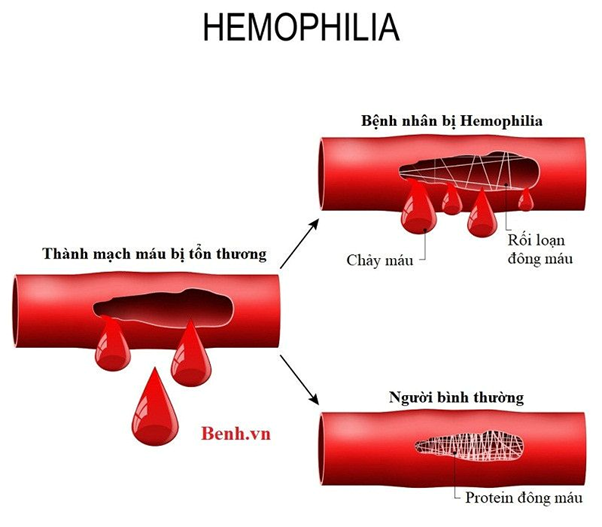

Vitamin K đóng vai trò quan trọng trong nhiều quá trình sinh học của cơ thể. Một trong những chức năng chính của nó là tham gia vào quá trình đông máu. Khi cơ thể bị thương, vitamin K giúp kích hoạt các protein đông máu, từ đó ngăn chặn tình trạng mất máu. Ngoài ra, vitamin K cũng có vai trò quan trọng trong việc duy trì sức khỏe xương và hỗ trợ chức năng tim mạch.

Quá trình đông máu là một phản ứng sinh lý cần thiết khi cơ thể gặp phải tổn thương. Vitamin K giúp sản xuất các yếu tố đông máu như prothrombin, một protein cần thiết để hình thành cục máu đông. Nếu cơ thể thiếu vitamin K, khả năng đông máu sẽ bị suy giảm, dẫn đến nguy cơ chảy máu kéo dài hoặc chảy máu không kiểm soát.

Đông máu không chỉ quan trọng trong trường hợp chấn thương mà còn trong các tình huống khác như phẫu thuật hoặc khi mắc các bệnh lý liên quan đến máu. Việc đảm bảo đủ lượng vitamin K trong chế độ ăn uống hàng ngày sẽ giúp cơ thể duy trì khả năng đông máu hiệu quả.

Một trong những triệu chứng phổ biến nhất của thiếu vitamin K là xuất huyết. Khi cơ thể không đủ vitamin K, khả năng đông máu sẽ bị suy giảm, dẫn đến tình trạng chảy máu kéo dài. Người thiếu vitamin K có thể dễ dàng bị bầm tím, chảy máu mũi, hoặc chảy máu chân răng.

Nếu không được điều trị kịp thời, tình trạng thiếu vitamin K có thể dẫn đến các biến chứng nghiêm trọng, bao gồm cả nguy cơ tử vong do mất máu.